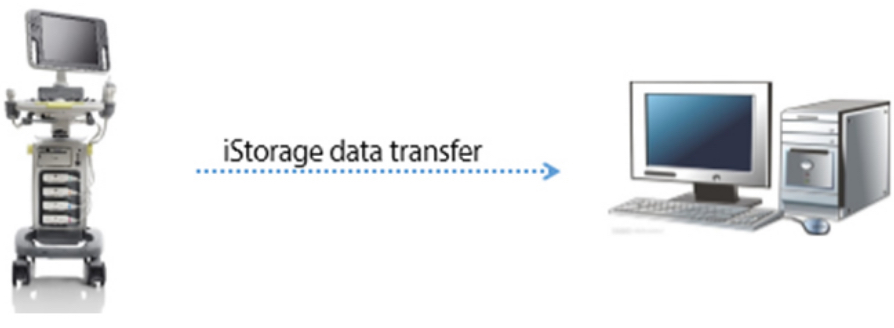

iStorage / iMeasurement / iReport

- iStorage: ???? ???? ?? ?? ? ???? PC? ?? ?????.

- iMeasurement & iReport: ??? ?? ?? ?, ?? ?? ? ??? ???? ?? ???? PC ?????.